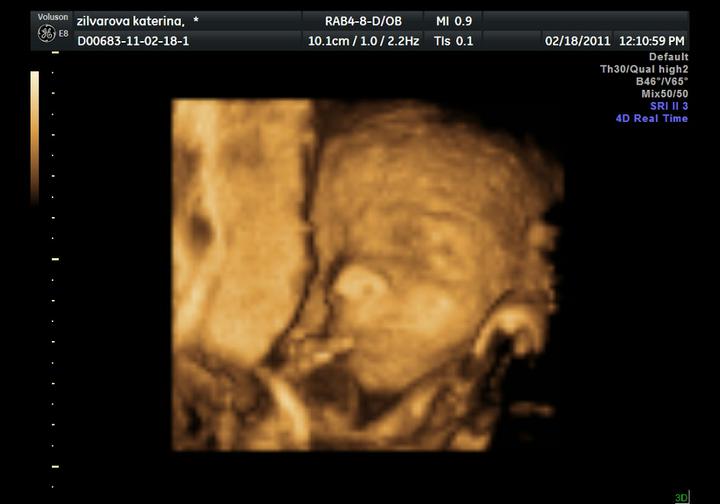

3D UTZ jsme si užili :o))) malá na nás vyplázla i jazyk :o)